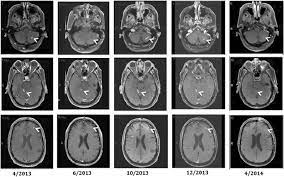

Prolonged Survival Of A Patient With Metastatic Leptomeningeal Melanoma Treated With Braf Inhibition Based Therapy A Case Report Bmc Cancer Full Text

Long Term Control Of Leptomeningeal Disease After Radiation Therapy And Nivolumab In A Metastatic Melanoma Patient Immunotherapy